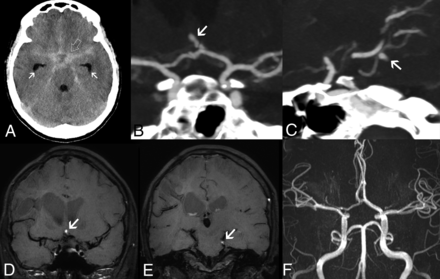

Intracranial aneurysms in adenosine deaminase deficiency. Axial unenhanced head CT scan in patient 5 at 16.4 years of age (A) demonstrates a diffuse subarachnoid acute hemorrhage (SAH) (open arrow) symmetrically distributed in the basal cisterns, horizontal segments of the Sylvian fissures, and anterior interhemispheric fissure, with mild enlargement of the temporal horns in keeping with incipient hydrocephalus (arrows). CTA images (B and C) reveal the presence of small-sized intracranial aneurysms of an anterior communicating artery branch (arrow) and the left superior cerebellar artery (arrow). Note that these 2 aneurysms have a peripheral location and arise in nonbranching sites. Follow-up brain MR imaging performed 23 days after the initial SAH episode, including coronal (D and E) black-blood T1WI, shows signs of intraaneurysmal thrombosis (arrows). TOF-MRA (F) does not depict flow-related signal within the aneurysmal sacs, in keeping with exclusion of the aneurysms from the circulation. These aneurysms remained excluded from circulation at 5-year follow-up.

Intracranial hemorrhagic strokes are additional complications of DADA2,1,2,6,11,12 involving nearly 12% of cases in a recent review6 and 17% in our cohort. These hemorrhages may occur in isolation1,12 or in association with ischemic strokes,2,12 as seen in our patients. In most published cases, no underlying causes were found. Conversely, 2 intracranial aneurysms were detected in 1 of our patients presenting with diffuse subarachnoid hemorrhage and a history of peripheral intracranial aneurysm and lobar hematoma. Of note, CNS aneurysms have been described only once in a patient with DADA21 and in a few patients with PAN who had unknown ADA2 status.16⇓-18 These aneurysms are multiple, small (<5 mm), and peripheral, arising in nonbranching sites or rupturing even when small.16⇓-18 Additionally, they can cause cranial nerve compression or infarction because of occlusion of the parental vessel.17 Their management is controversial, with both medical and surgical and interventional treatments proposed.17 In our case, early follow-up studies demonstrated spontaneous aneurysmal thrombosis with total exclusion from circulation and no new intracranial aneurysms after 5 years. Of note, no visceral aneurysms were found in this patient and in the other investigated patients.